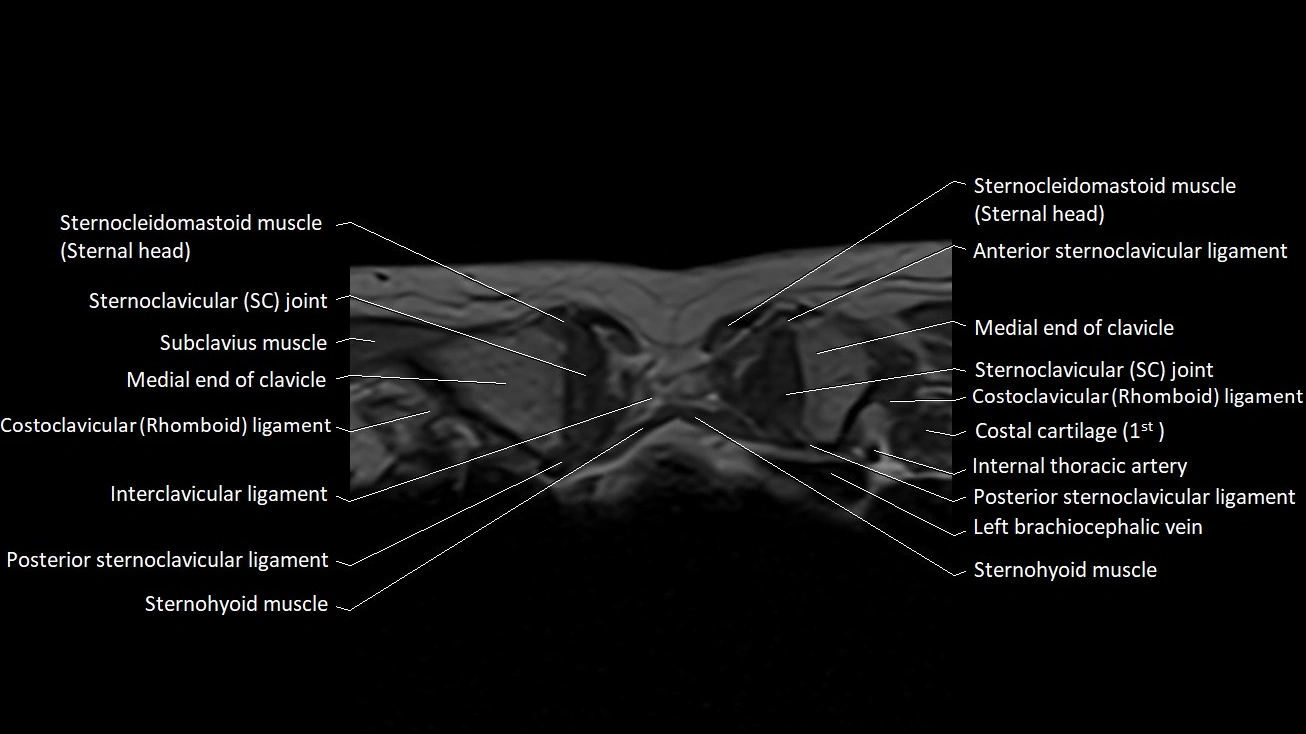

MRI images

image